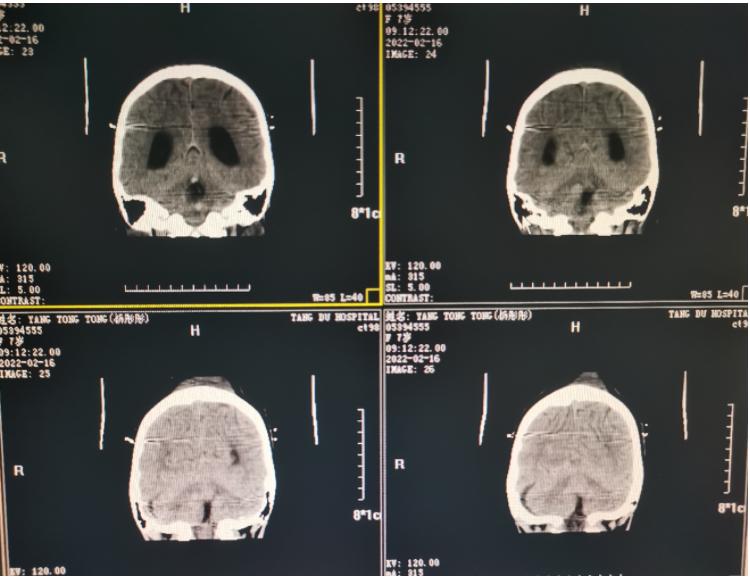

术后影像学资料:

手术做完后Amy的呕吐和头疼症状得到了明显地缓解,不久后孩子就回归了正常的学习生活,现在已经开心的坐在教室上课了。